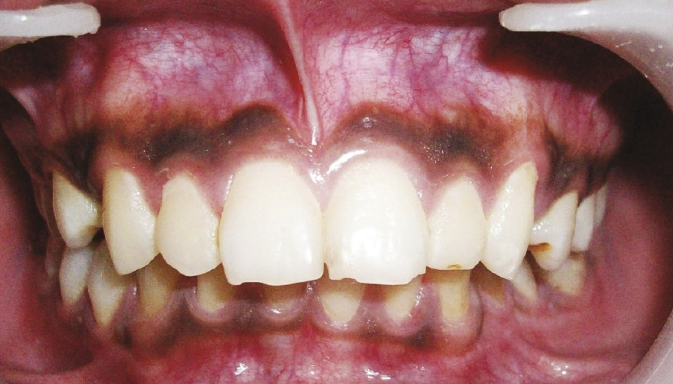

most commonly observed in patients of color, variant of normal

melanin pigmentation